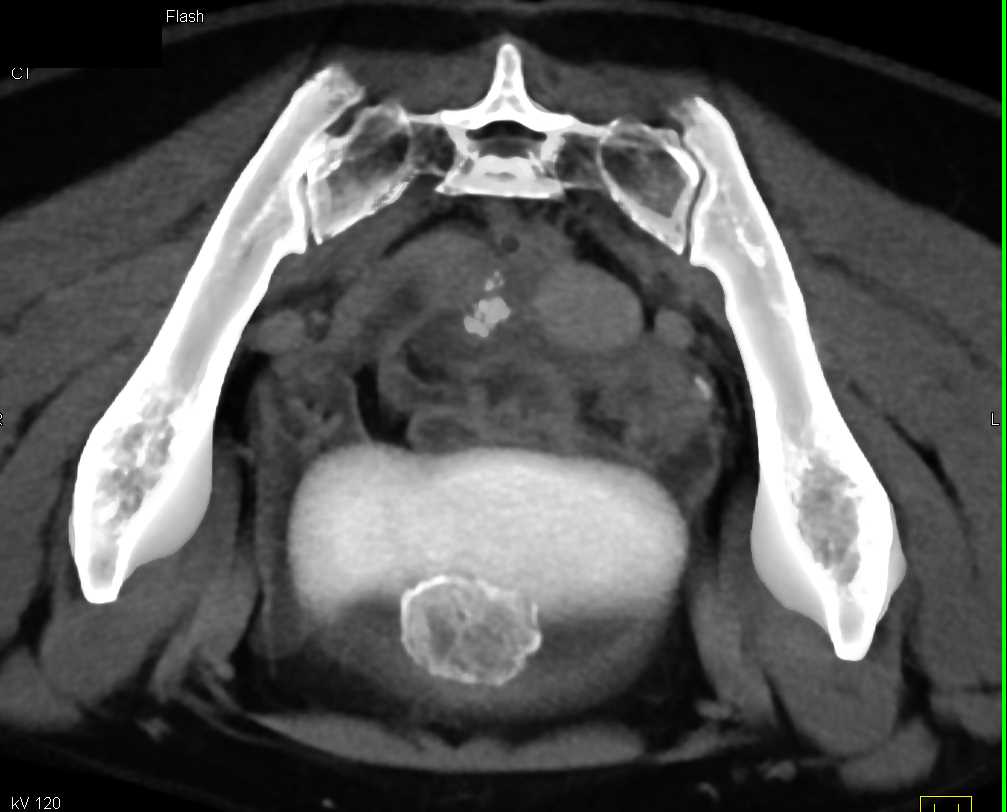

Urachal Carcinoma of the Bladder